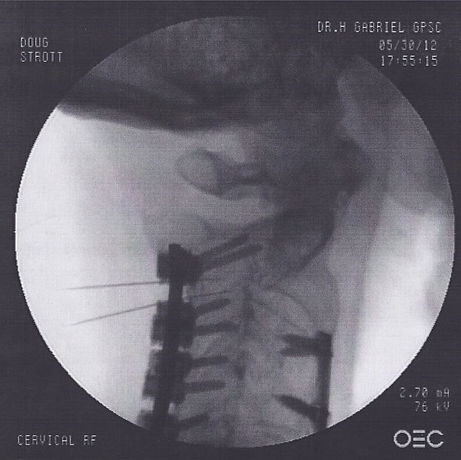

The nurse had me lay on my stomach on a table and then I was placed under a fluoroscope so Dr. Gabriel could accurately place the needles in my facet joints.

Below are photos of the procedure.

Left side C2-C3, C3-C4

Right side C2-C3, C3-C4